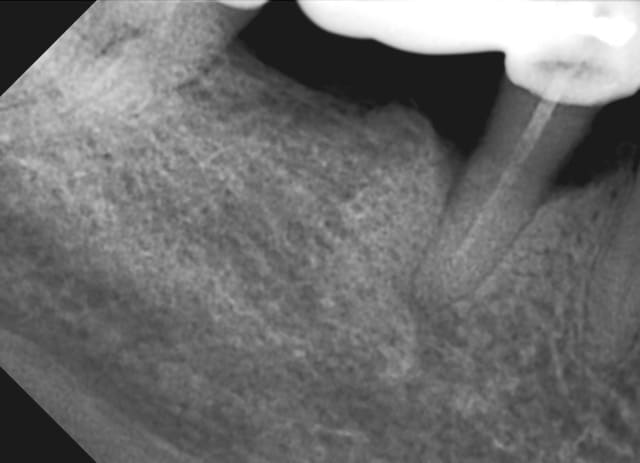

Patient se présente 2 mois avant la pose d'une prothèse totale de genou. Aucun problème ressenti au niveau de ses dents, le suivi a été régulier chez son dentiste.

Que pensez vous de ces dents (le sondage est à la hauteur de ce qu'on voit sur les radios: poches entre 3 et 8 mm sur ces dents)? L'atteinte des furcations est-elle suffisante pour justifier des extracs, ou vous tenteriez de la chir paro pour rétablir tout ça, quitte à déplacer l'intervention orthopédique?

Parce que des atteintes de furcation de stade 1 à 3 comme ici représentent, me semble-t-il, un état altéré des dents et des gencives, susceptibles de se transformer en état inflammatoire aigu (infecté) d'un jour à l'autre.

Et quand tu as une prothèse articulaire, ses surfaces peuvent être colonisées par les bactéries buccales qui entreraient dans le système lors d'un tel état. On peut observer alors un descellement de ces prothèses ou une infection à leur niveau, ce qui nécessite une réintervention.